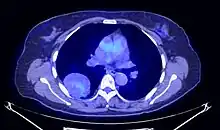

En tomodensitométrie[20],[31], quelle que soit la localisation, une tumeur fibreuse solitaire apparaît comme une masse tissulaire ovoïde ou lobulée, bien délimitée, refoulant les structures voisines sans les envahir. Elle se rehausse fortement après injection de produit de contraste. Les tumeurs de petite taille sont homogènes, mais les plus volumineuses présentent des plages hétérogènes de nécrose et d'hémorragie intra-tumorale. Il n'y a pas habituellement de calcifications et, lorsqu'elles sont présentes, elles sont de petite taille[31]. Les tumeurs malignes peuvent se présenter accompagnées de nodules pulmonaires métastatiques, et tendent à être plus volumineuses et plus hétérogènes[42].

Le TEP scanner est utilisé afin de caractériser l'activité métabolique de la tumeur et de la différencier des tumeurs malignes. Le traceur est fixé de manière hétérogène et peu intense[41],[23].